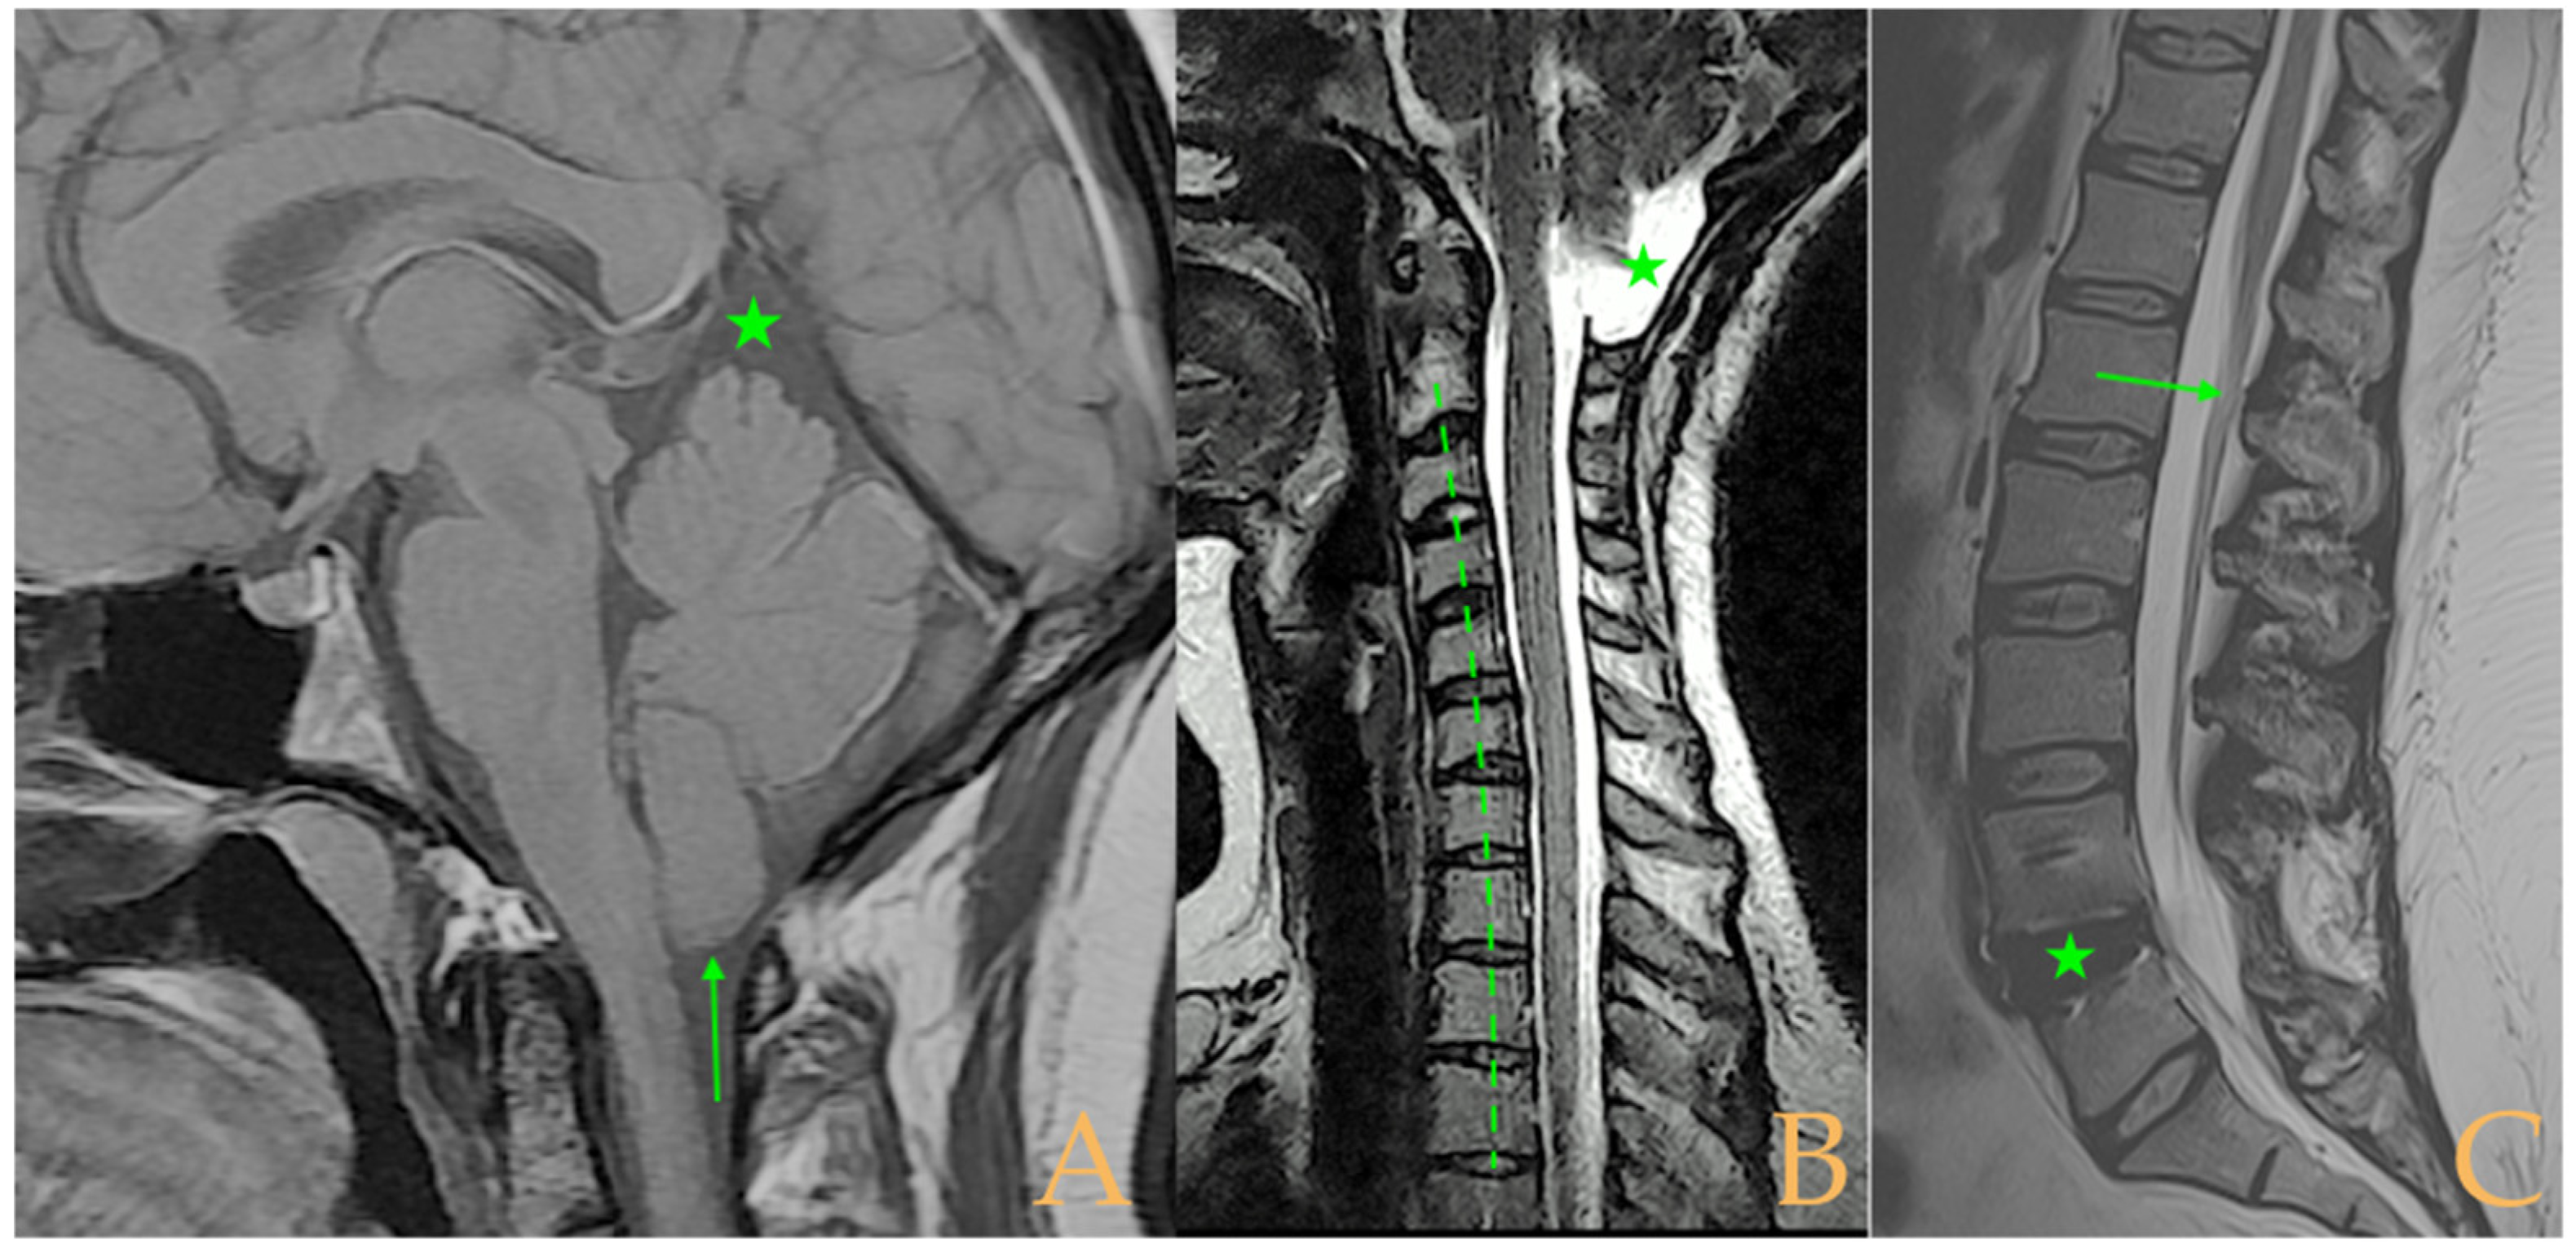

The MRI showed descent of the cerebellar tonsils, 13 mm pineal cyst, and multiple disc protrusions in T4-T8 and T9-T10, with herniation T5-T6. Straightening of the thoracic and lumbar spine. Low conus medullaris at the upper third level of the L2 vertebra (Figure 7). The full-spine X-rays showed a mild double-curved thoracic and lumbar scoliosis (<10° Cobb), and lower extremity dysmetria with shortening of the left lower extremity estimated to be 3 mm at the level of the acetabular roofs and 7 mm at the level of the iliac crests. Dextroconvex lumbar scoliosis was estimated to be 2°, and levoconvex cervicothoracic scoliosis was estimated to be 10° (both total, including all vertebrae). The estimated lateral curves, including all vertebral bodies in each region, were cervical lordosis 25°, thoracic kyphosis 34°, and lumbar lordosis 53°.

Figure 7. Imaging of patient 7. A: Descent of the cerebellar tonsils (star); B: straightening of the cervical spine (interrupted line) with image suggestive of medullar ischemia (arrow); and C: straightening of the upper part of the lumbar spine (interrupted line) and conus medullaris at the level of the upper third of L2 (arrow).